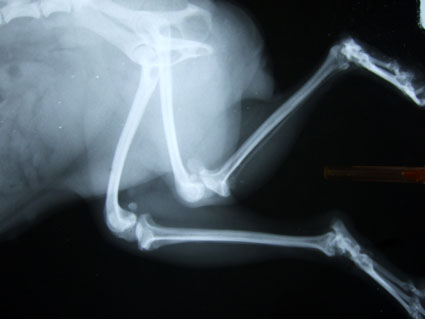

茶茶的雙腿,罹患的就是小型犬常見的膝關節異位.

因而延誤了茶茶的黃金治療期,讓左後腿因而嚴重變形,卷縮而無法使用.

剩下的右後腿,也有同樣的問題.

而且也因為這是唯一可站立的後腿,讓全身重量擠壓在這條腿上,更是會加速膝關節的惡化.